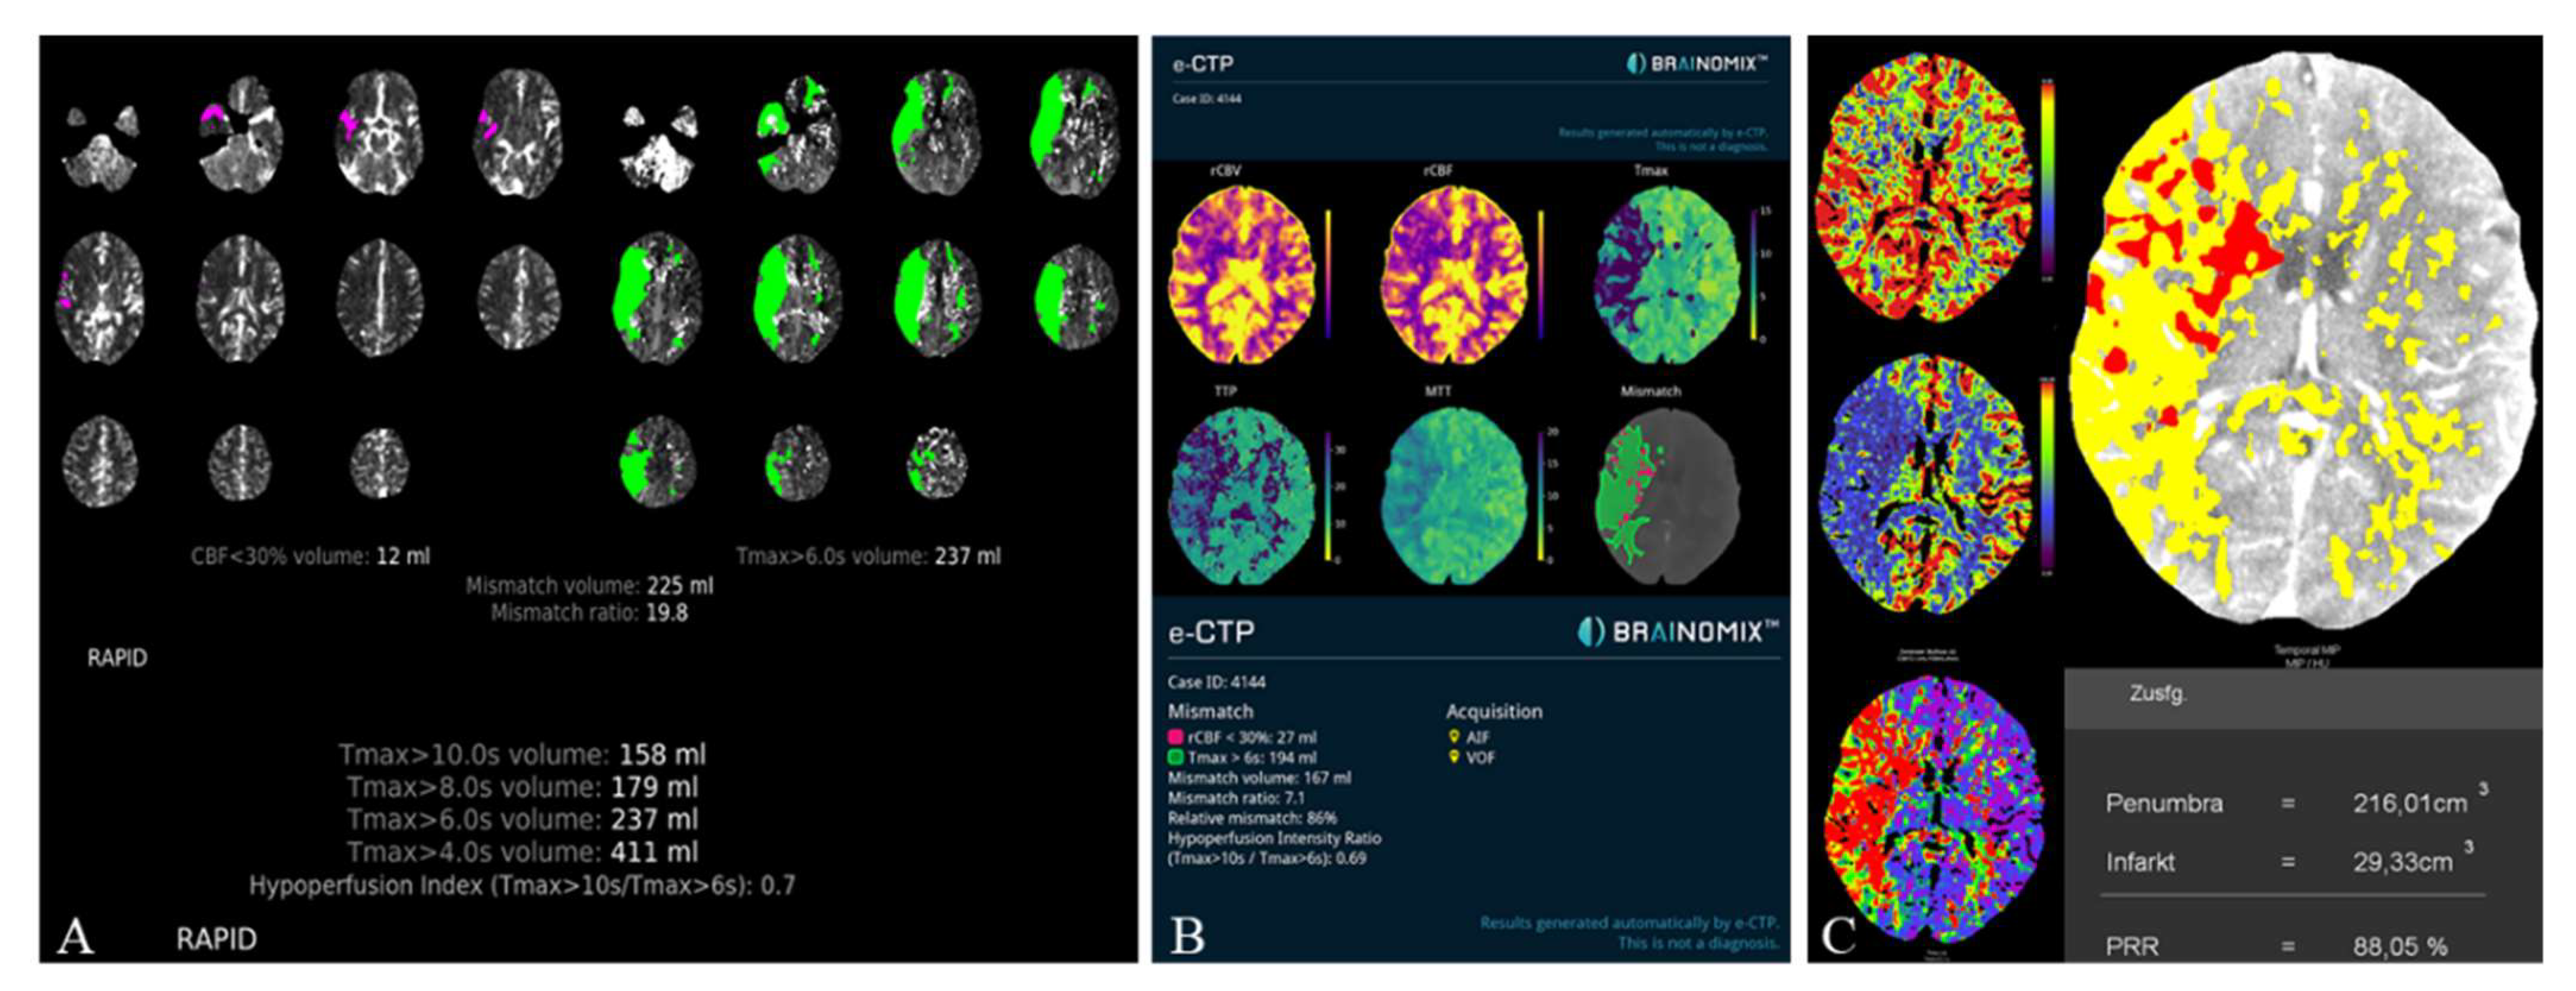

2.1.3. Automated CT Perfusion Software